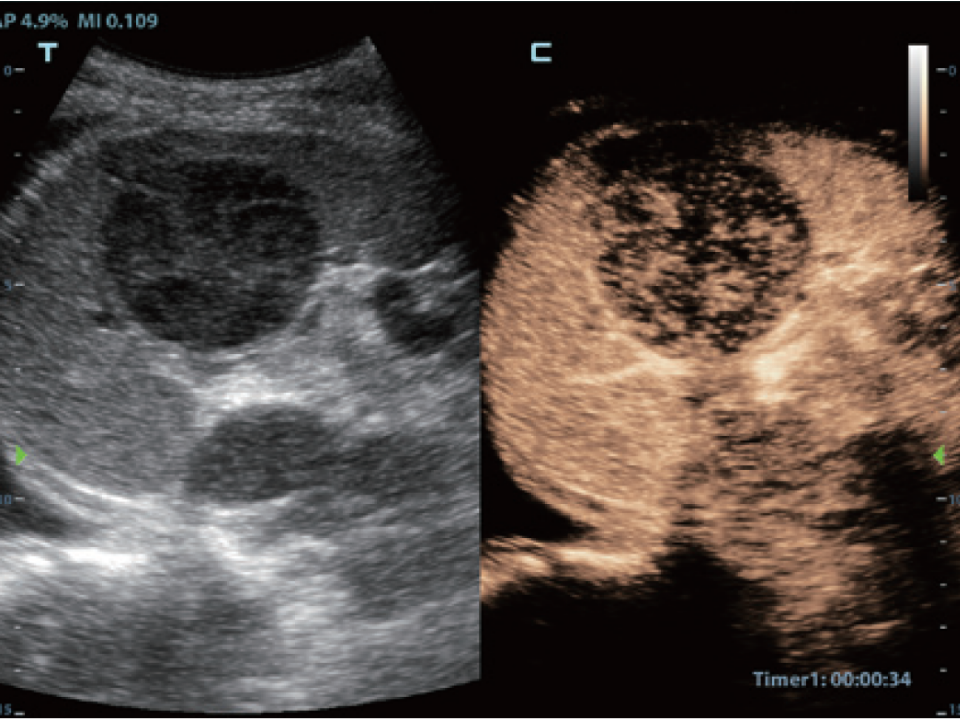

- Contrast Imaging